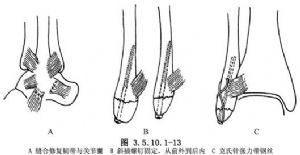

(3)不穩定性踝部骨折常有外踝以外它處骨折同時存在,則手法雖易整復內踝及距骨,但由於外踝斜折或粉碎骨折及下脛腓分離,距骨因外側韌帶牽拉,向外側再移位或傾斜,而使病情複雜,需統籌處理(圖3.5.10.1-13)。